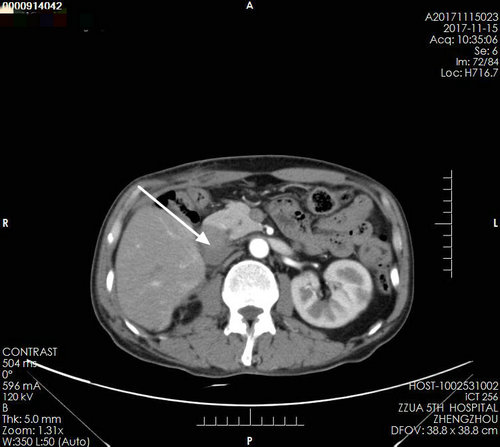

▲ 术后复查影像

术后复查:下腔静脉通畅,腔内CT值均匀,未见填充物,右肾区由肠管填充,未见肿瘤残留及复发。